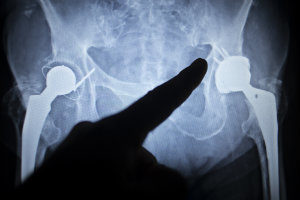

Metal on metal hip replacement xray complicationsUnfortunately, many have suffered serious complications from a metal-on-metal hip replacement.

In basic terms, the hip joint is a synovial joint; the ball is the femoral head and a round cup-shaped structure known as the acetabulum is the socket for the hip joint. This ball fits into the socket and bands of tissue called ligaments connect the ball to the socket. As you move your legs, the femoral head (the ball) at the top of the femur slides against the acetabulum (the socket) of the pelvis.